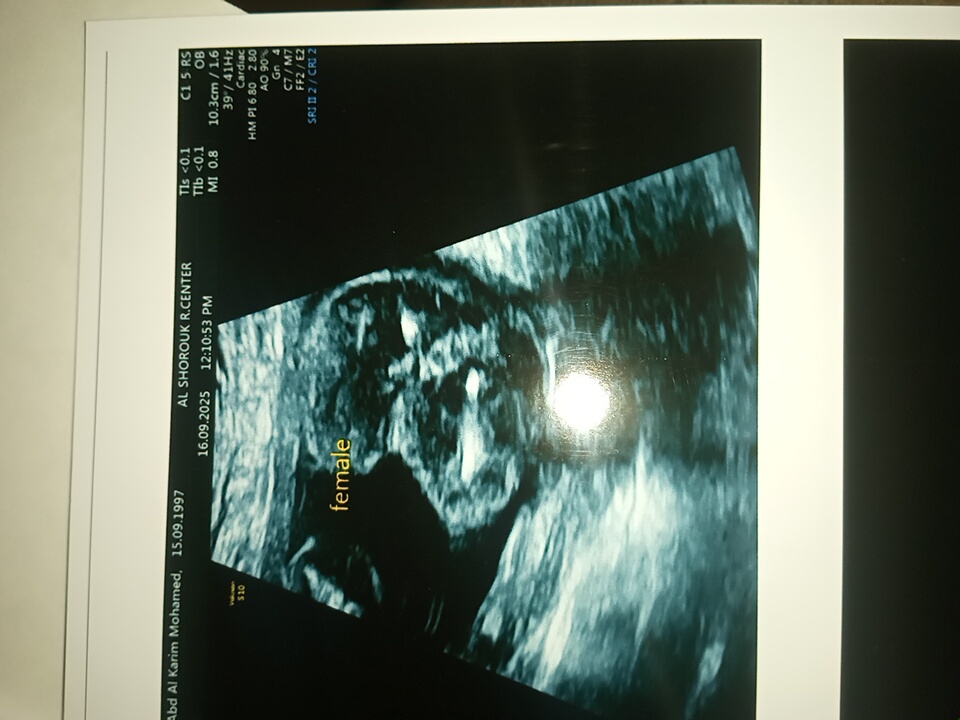

نوع الجنين اختلف من اول الخامس